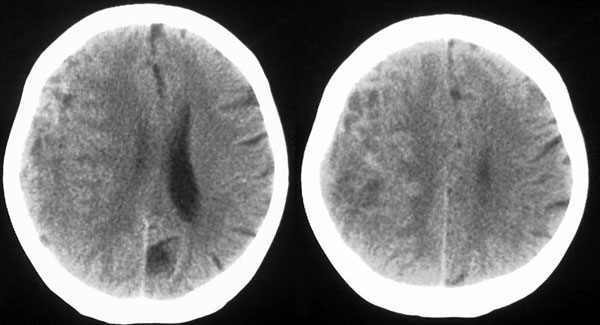

女87左下肢麻木,无外伤史

右颞顶部颅骨内板下新月形混杂密度影,右大脑皮层受压内移,考虑慢性硬膜下血肿,建议增强一下看看病灶,因为平扫好像显示的不是很好;左顶部软化灶

右侧大脑半球脑沟 脑裂变浅或消失,顶叶不规则低密度影,右侧侧脑室明显受压移位,中线偏移,右侧内板下新月形混杂高密度致密影,多考虑:慢性硬膜下血肿.必要时建议强化扫描.

右额颞顶部颅骨内板下方新月形混杂密度影,同侧灰白界限受压内移,右侧脑室呈受压性改变,中线结构左移;左顶叶扫及片状脑脊样低密度区,另可见部分脑沟增宽

ct印象:1.右额颞顶部慢性硬膜下血肿

2.左顶叶软化灶

3.脑部分萎缩

右额颞顶部颅骨内板下方新月形混杂密度影,同侧灰白界限受压内移,右侧脑室呈受压性改变,中线结构左移;应该是右额颞顶部慢性硬膜下血肿,建议mri检查。

右侧脑室前角受压变小,中线左移,考虑慢性硬膜下血肿.左侧脑软化灶.

右侧颞顶颅内板下可见新月状高低混杂密度影,右侧脑沟回消失,脑组织受压中线结构左移,考虑为右侧慢性硬膜下血肿。病人情况允许可做mri检查。我们遇到过几例没外伤史的病人有硬膜下出血的,多为六七十岁的老年患者,不知慢性硬膜下血肿与年龄有关否?